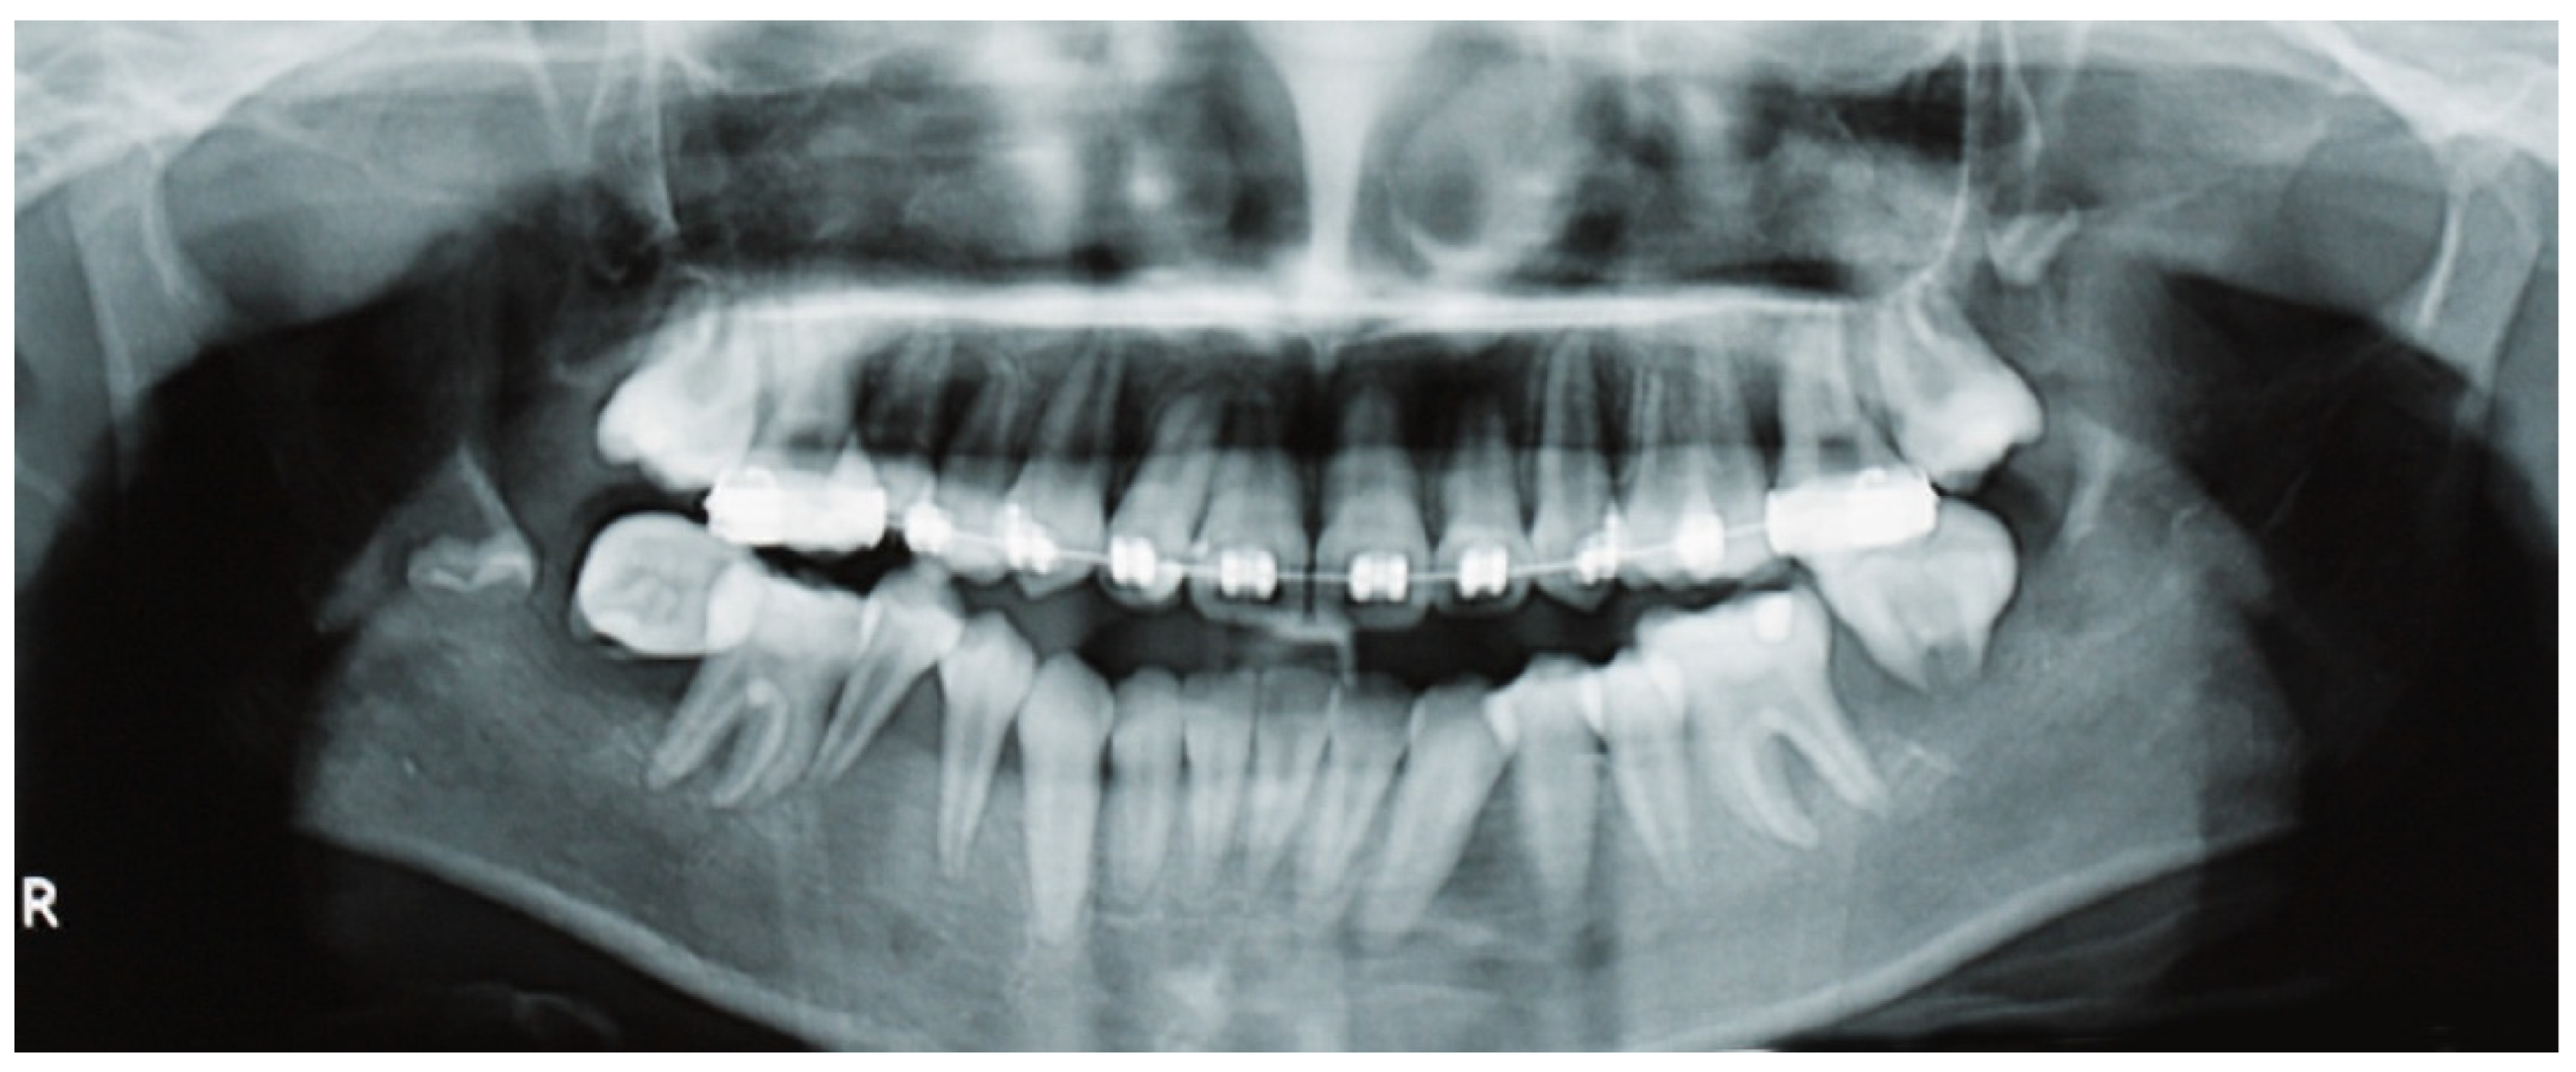

A panoramic radiograph revealed ill-defined radiolucencies in the posterior mandible bilaterally, related to the adjacent permanent teeth, which also showed a ‘floating teeth’ appearance (Figure 2). Moreover, computed tomography showed hypodense (soft tissue) masses along and distal to the mandibular ramus extending upwards into the maxillary sinuses, bilaterally (with dimensions of 1.5 × 3.0 × 7.0 cm and 1.7 × 1.2 × 3.5 cm on the right and left side, respectively), as well as the posterior wall of the right orbit; also, there was a perforation of the right mandibular cortex along the second molar tooth (Figure 3 a,b). Based on the clinical and imaging findings, the differential diagnosis mainly included hematologic neoplastic conditions, such as lymphomas, leukemias, and Langerhans cell disease; the possibility of sarcomas, such as rhabdomyosarcoma or Ewing sarcoma, was also considered, especially considering the patient’s age.

Figure 2.

Panoramic radiography shows ill-defined radiolucencies in the posterior mandible bilaterally, affecting the adjacent permanent teeth that resemble a ‘floating teeth’ appearance. In this particular focal trough, the osteolysis appears to be more diffuse in the right mandible, extending into the premolar region and also causing the displacement of the sperm of the third molar.